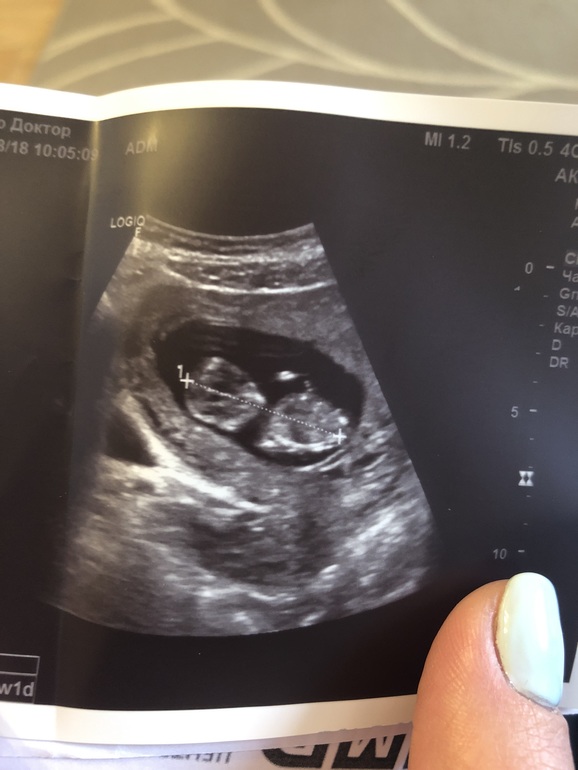

В общем посмотрели меня, УЗИ сделали. Сказали все ок, воды на месте, малыш активный, срок по КТР на 4 дня опережает))) Но ошарашили гематомой и узлом в матке(типа миома, никогда у меня не было). Прописали дюфастон, валерьянку и прочее, как обычно. Но я в шоке, конечно, особенно от миомы. Уже начиталась что плохо это очень при беременности. Расскажите, у кого-то было подобное? Что-то с ней делать надо или сама рассосётся? И про гематому расскажите, в первые беременности не было в меня такого... Я так понимаю она сама должна выйти или рассосаться?

Заключение УЗИ

Ну и фоточку выложу, может кто пол сможет предположить?))) я смотрю тут многие понимаю что-то по этим снимкам))))))